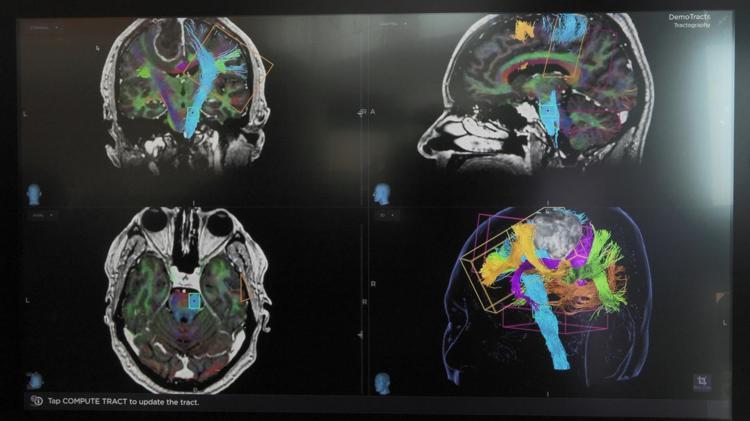

Prof. Dr. Günel, "Anevrizmalar beyin tümörleri ile beraber maalesef beyin cerrahisinde ilgilendiğimiz en ağır hastalıklardan biri. Biz yaklaşık 30 yıldıra yakın zamandır hem anevrizmaların hem beyin tümörlerinin genetik yapısını anlamaya çalışmak için çalışmalarımızı devam ettiriyoruz. Eğer yakın ailenizde iki veya daha fazla kişi beyin kanaması ya da anevrizma tanısı konulduysa büyük ihtimalle genetik bir yatkınlık olabilir.  Bu hastalarda sigara kullanımı ya da yüksek tansiyon gibi risk faktörleri varsa, bunların tedavi edilmesi gerekebilir. Ayrıca beyin damarlarını görmemizi sağlayan MR anjiyo ya da tomografi ile test yapılması lazım. Radyolojik yöntemler dışında bu anevrizmaların kanamadan tespiti gibi bir teknik yok. O yüzden yakın ailesinde iki veya daha fazla beyin kanaması ya da anevrizma teşhisi konulmuşsa, 30 yaşından sonra özellikle risk faktörlerini de taşıyorsa, radyolojik yöntemlere başvurması gerekiyor" dedi.

Hem anevrizmalar hem de hipertansiyon, diyabet gibi diÄŸer yaygın kronik hastalıkların hepsinin yavaÅŸ yavaÅŸ genetik temellerini anlamaya baÅŸladıklarını da kaydeden Prof. Dr. Günel, şöyle devam etti: "Anevrizmalarla ilgili konuÅŸacak olursak, bu sayede kesin bir ÅŸekilde erken tanı koyabileceÄŸiz ki, kanama olmadan, sekeller ortaya çıkmadan hastalığı belirleyebilelim. Tedaviler de kanama olmadan çok daha güvenli. Önceden tanı koymak için genetik temellerin belirlenmesi lazım "Â

Anevrizmanın genetik temellerini yıllardır sürdürdükleri çalışmalarla belirlemeye başladıklarını anlatan Prof. Dr. Günel, bu verilerin uzun yıllar takip edilecek çok büyük hasta gruplarında yapılacak çalışmalarla kanıtlanması gerektiğini ve bu nedenle çok büyük çaplı yeni bir araştırmaya hazırlandıklarını vurguladı. Prof. Dr. Günel, 5 yıl sürecek dünyanın en kapsamlı araştırmalarından biri olan projeleri için Amerikan Ulusal Sağlık Enstitüsü NIH'e başvuru yaptıklarını da anlatarak şu bilgileri verdi:

"Örneğin bir kan örneği alıp oradan DNA çıkarıp sekanslamasını dizilenmesini çıkardığımız zaman, hemen hemen tam olarak sizin riskinizi belirleyebiliyoruz. Ama bu, ancak yüzdeler şeklinde olabiliyor, yüzde 10 olsa bile, tam olarak anevrizma gelişeceği belli değil. Genetik, yüksek tansiyon, sigara içme gibi diğer faktörlerle birleşince, bu risk artabiliyor. Aynı zamanda beyin damarlarının yapısı da çok önemli. Bunların hepsini biraraya koyduğumuzda bu yoğun denklemlerle artık insanların riskini belirlemeye başladık.

Bunun için yeni bir çalışma baÅŸlatıyoruz, Amerika'da bu çalışmayı yapmak üzere hükümet kaynaklarına baÅŸvurmak üzereyiz. Amerika'daki 30 merkezin 6 bin ile 7 bin 500 hastanın dahil edilmesi planlanıyor. Bu hastaları kanamadan önce bulmak, kanama olursa kanamadan sonra takip etmek, 3 veya 6 ay sonraki takiplerinde ne durumda olduklarını anlamak için bakacağız. Bunun bütçesi milyonlarca dolar çok büyük bir bütçe. İlk olarak bu ÅŸekilde baÅŸlayıp genetik riski de belirleyerek, özellikle kanama sonrası damarların tıkanması, felce yol açması; bunların da genetik alt yapısını araÅŸtırmaya yönelik 7 bin kiÅŸi küçük küçük bir rakam; ancak baÅŸlangıç için güzel bir rakam."Â